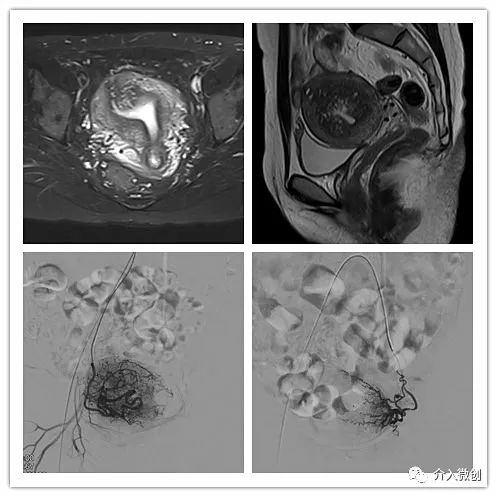

青年女性患者,痛经近10年,近5年痛经明显加重。确诊为子宫腺肌症(弥漫型),经放置曼月乐、注射亮丙瑞林等妇科保守治疗,症状缓解不理想,痛经进行性加重,严重困扰工作与生活。

- 行子宫腺肌症介入栓塞治疗

- 插管至右侧髂内动脉造影,显示右侧子宫动脉

- 插管至右侧子宫动脉,显示子宫右侧病灶情况

- 插管至左侧子宫动脉,显示子宫左侧病灶情况

- 术前MRI显示子宫明显增大,病灶主要位于子宫前壁

术前MRI显示子宫明显增大,病灶主要位于子宫前壁

术后3个月复查MRI显示子宫明显缩小,前壁病灶萎缩坏死